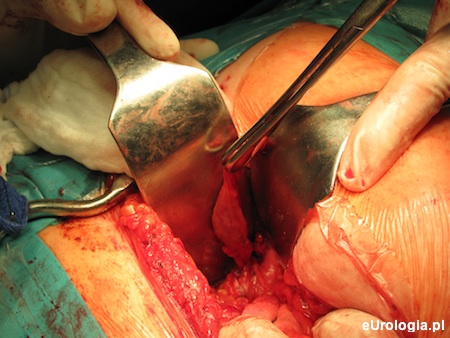

Na podstawie opisywanego przed laty wystąpienia VUR po prawej stronie, obraz cystoskopowy pęcherza moczowego oraz utrzymujący się przez lata ropomocz o niejasnej etiologii, wysunięto podejrzenie ropniaka kikuta moczowodu. Pacjentka została zakwalifikowana do leczenia operacyjnego. Cięciem Pfannenstiela otwarto pozaotrzewnowo jamę brzuszną, uwidaczniając poszerzony kikut moczowodu w licznych zrostach i nacieku zapalnym. Ze względu na trudne warunki śródoperacyjne, zdecydowano o otwarciu pęcherza moczowego, wycinając rozetę w rzucie ujścia prawego moczowodu i usuwając kikut w całości.

Rycina 2. Wypreparowany kikut prawego moczowodu.

Ureterocele współistniejące z moczowodem podwójnym w blisko 80% przypadków powiązane jest z moczowodem odchodzącycm od górnego segmentu nerki podwójnej. W większości przypadków ureterocele nie powoduje istotnego stopnia zaburzenia odpływu moczu z górnego segmentu nerki. Leczenie ropniaka kikuta moczowodu polega na jego chirurgicznym usunięciu. Miejscowy odczyn zapalny oraz bliskie sąsiedztwo naczyń biodrowych sprawiają, że wycięcie ropniaka może być dużym wyzwaniem dla operatora. W celu lepszego uwidocznienia kikuta moczowodu zaleca się szerokie uwolnienie pęcherza moczowego. Otwarcie pęcherza moczowego i wycięcie rozety wokół zanikowego ujścia moczowodu znacznie ułatwia wypreparowanie moczowodu.